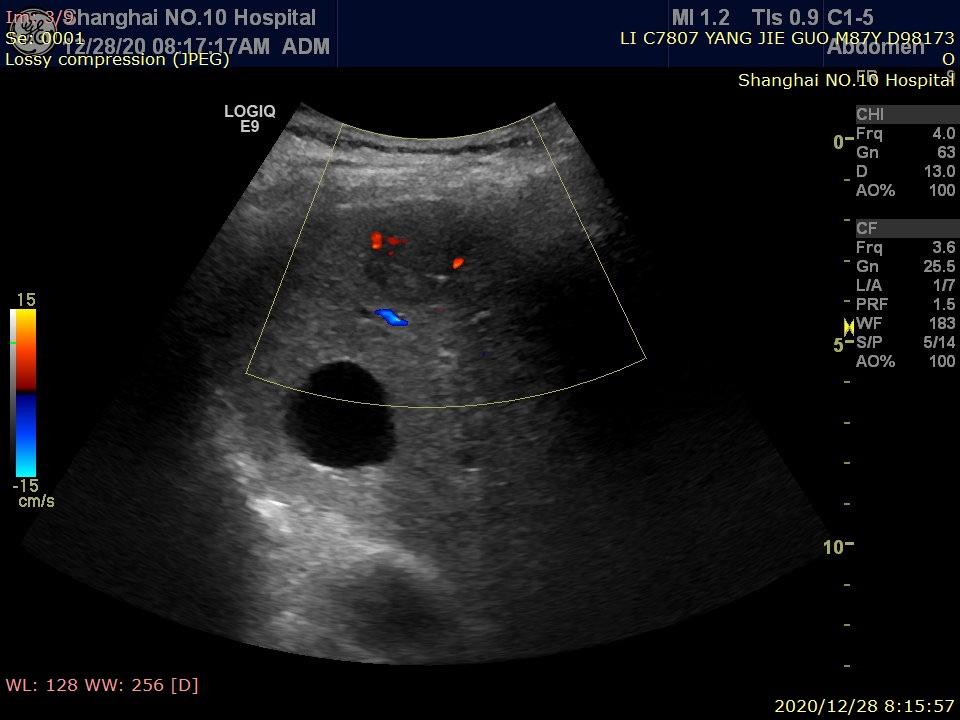

彩超发现肝占位,提示肝癌

图片尺寸1672x1199